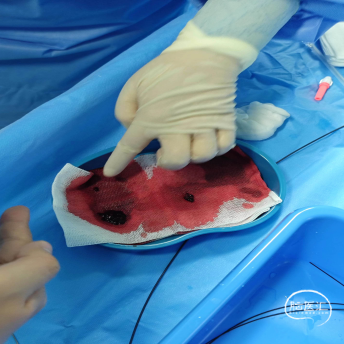

反复抽吸,多次中间管于负压状态下无回血时,负压状态撤出体外,可见大量血栓。